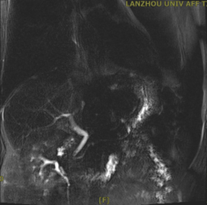

近日,兰州石化总医院(甘肃中医药大学第四附属医院)普外科团队成功为一名78岁男性患者实施腹腔镜下胆囊切除术+3mm超细胆道镜下经胆囊管胆总管探查取石+一期缝合术。该患者因反复发作胆源性胰腺炎多次住院,此次术前影像学(腹部MR)提示胆囊多发结石,胆总管并未发现明显结石影,经科室讨论后决定术中行经胆囊管胆总管探查。